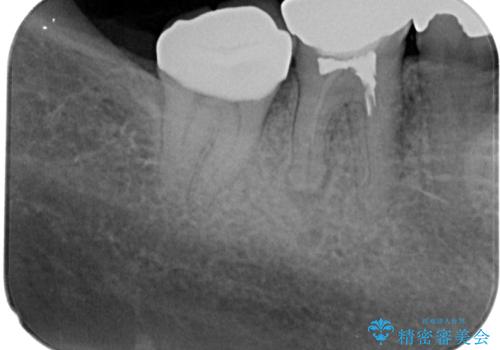

右下の銀歯が外れた オールセラミッククラウン

- 右下の銀歯が取れたとのことで来院された患者様です。脱離をしたメタルインレーを戻してみましたが不適合を認めました。メタルインレーの範囲が大きく、残っている歯の範囲を考慮してオールセラミッククラウンにて補綴治療を行っていくことにしました。

拡大鏡視野下で虫歯の除去を行い、オールセラミッククラウンに適した形に整えました。

歯と歯茎の間に圧排糸と言われる糸を入れてシリコーン印象材にて型どりをしました。

精密印象時、唾液の量が多かったため個歯トレーを使用しています。